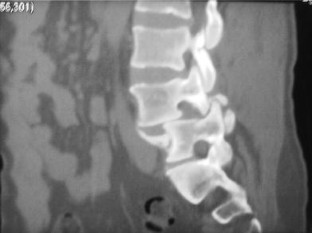

We report a case of L4–L5 traumatic anterolisthesis. The patient was treated surgically 4 months after the injury. His radiological and operative findings showed L4 inferior facet tip fracture, L4–L5 anterior displacement and left L4–L5 foraminal disc protrusion. Decompression, reduction with L3, L4, L5 pedicular screw fixation, L4–L5 disc excision and interbody cage insertion with autologous bone grafts were done. Flexion type injury was thought to be the probable mechanism.

Fig. 2